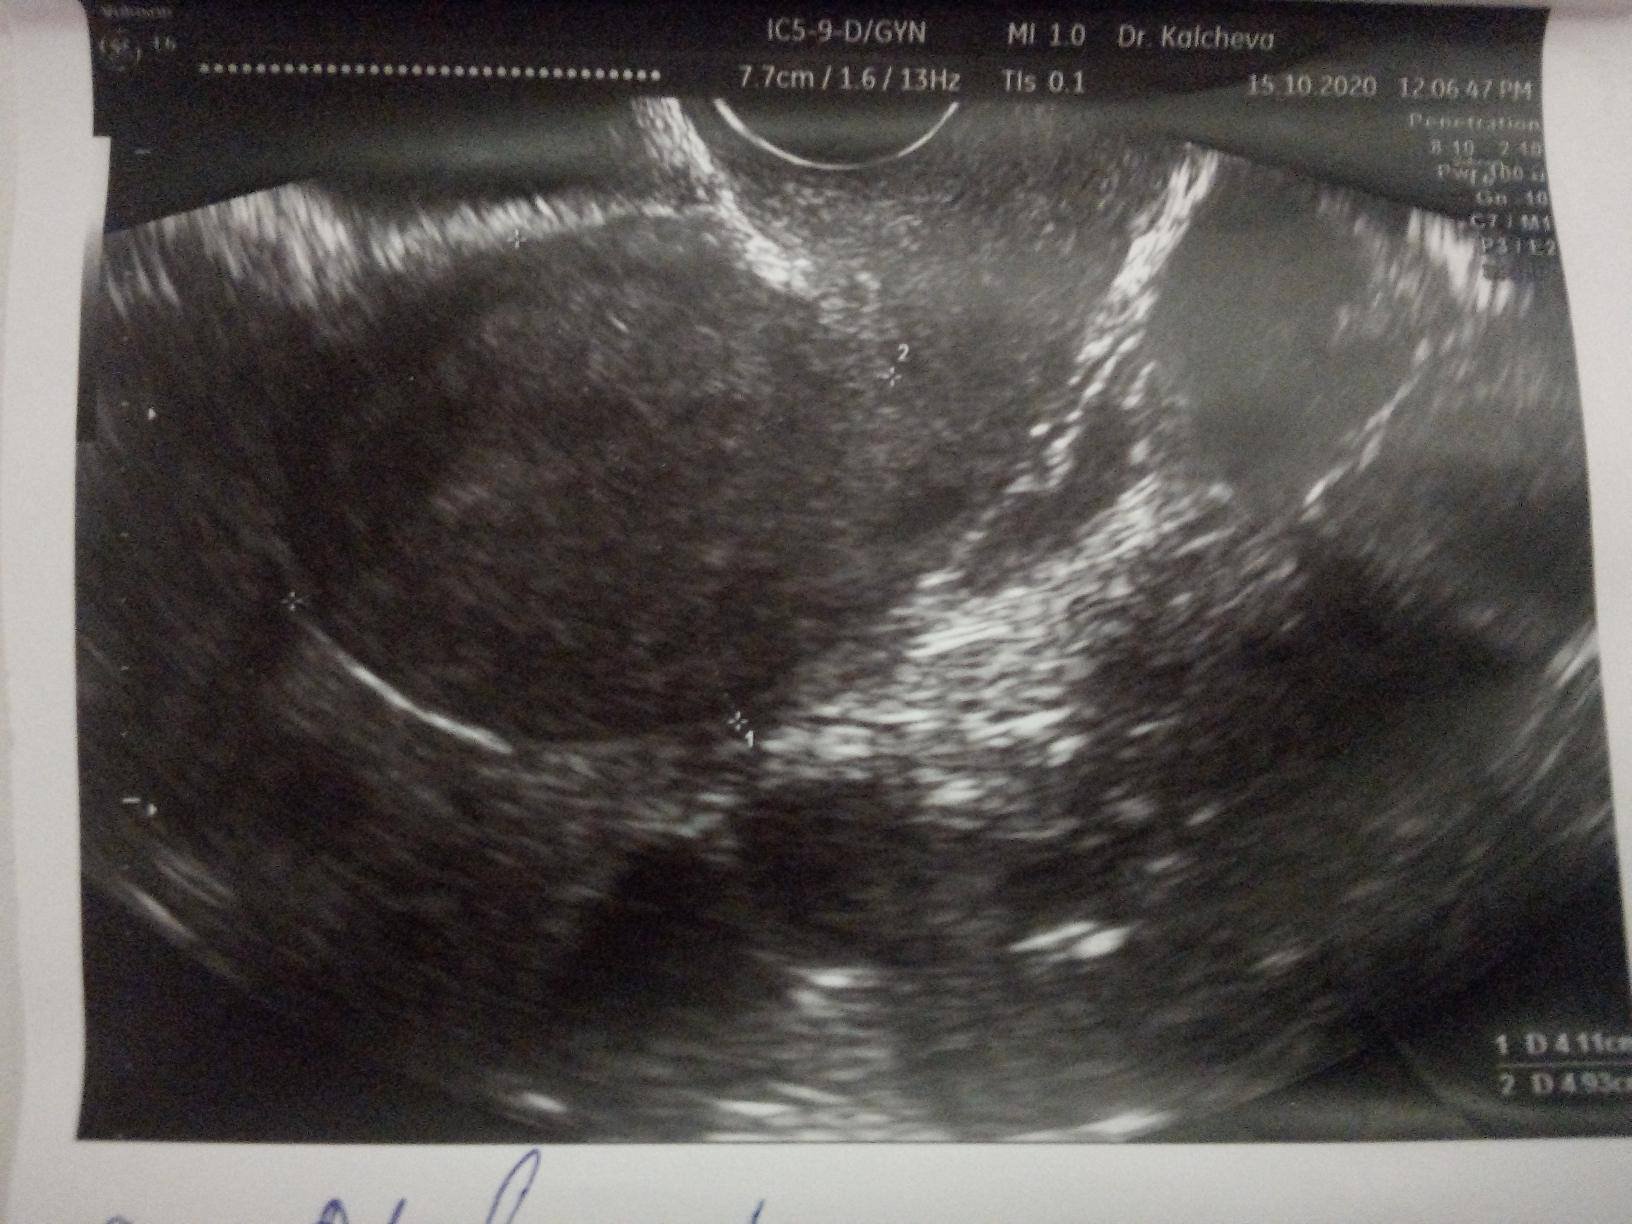

Първо да започна с това, че съм раждала. Детето ми е на 6 години и откакто родих от гърдите ми изтичаше капки "мляко" при стискане. Така 6 години. Един хирург ми каза, че не е нещо необичайно при раждали жени, отворени канали, затова и не го счетох за проблем. През това време съм нямала проблем с менструацията, овулацията и т.н. Последните 2 години бях "въздържала се" от сексуални контакти. Потънах в работа и отговорности, малко сън (понякога за 2 дни по 1-4 часа сън, дневни и нощни смени). Казвам го, защото мисля, че има отношения спрямо хормоните. Извинявам се, ако е излишна информация. След това, тази година имах момент на силна емоция. Съвпадна и със започването на нова работа. След това получих подуване на едната гърда, червенина, болка и на мястото на червенината затопляне. Помислих мастит и почнах Клиндамицин, но не изключвах най-лошия вариант. Ходих на ехограф на гърдите (бях се побъркала от мисли да не е рак на гърдата) - ехографията не показа нищо проблемно, т.е. освен запушена жлеза. След това с ехографията отидох при мамолог. Мамолога направи прегледа, видя ехографията и каза, че няма притеснително, но иска да изследвам пролактина, одобри и използването на Клиндамицина, от който всъщност ми мина гърдата. Нямах възможност да направя изследване на пролактина. След "сексуалната диета" и т.н. (дълга и широка) имах полов акт с любимия човек. 2-3 дни след това гърдите спряха да ми "сълзят" капки. Помислих, че всичко се нормализира вече. Бях изключила за датата ми на менструация и докато правихме секс ми дойде точно на датата, на която си ми идва - 27ми (това по-миналия месец). Месечния ми цикъл е от 29-30 дни, т.е. ми идва на същата дата всеки месец, най-много да ми подрани с 1 ден, но не закъснява. Октомви месец прокървях на 13-ти (по-точно полунощ на 12ти, затова казвам 13-ти). Първоначално беше кафеникаво, оскъдно зацапване. След 2 дни стана кафеникаво-червеникаво, пак леко течащо. Така до 16-17ти. Беше ми станало много лошо в първите дни, затова и потърсих един приятел да ме закара до болницата - виеше ми се свят и не бях сигурна в ходенето си (световъртежи и замаяност - имам мъдрец за изкарване, който явно е засегнал ухото, защото имах удебеляване леко зад ухото и като натиск, заради което почнах антибиотик Оспамокс 1000 и след него световъртежите минаха, но като го спрях седмица по-късно пак лека-полека почнаха, т.е. явно от зъба и трябва да го махна - първото, което ще направя). Та, ходих на гинеколог. Прегледа ме с вагинален ехограф по време на въпросното кървене (на 15-ти). Даде ми снимки. Каза, че нямам миоми, кисти и подобни. Че кървенето е на хормонална основа. На снимките се виждат фоликули (до колкото разбирам). Има малки с големина 1 см и нещо до 1 по-голям с размери близо до 5 см (явно доминантния фоликул). Каза ми "Когато сега ти дойде на датата, на която трябва, това в момента не го брой за менструация, на 2-3 ден от първия ден на менструацията направи изследвания на LH, FSH, Testosteron, Estradiol, Prolactin, а на 22-23 ден, считано от 1-я ден на менструацията на Progesteron. Това кървене е хормонален дисбаланс, който може да се дължи на стрес". След това бях с любимия човек от 21 до 24-ти Октомври, като може би беше 22-23ти, когато каза, че се е изтървал. Казах му, че не съм в овулация, не би трябвало, считайки, че когато кървях ми е била. Дойде 26-ти - няма менструация, 27-ми - няма менструация и така до ден днешен - от 27-ми Октомври чакам менструация, но няма. Днес е 11-ти ден закъснение, считано от 27-ми насам. Правих въпреки всичко тест за бременност за всеки случай на 30-ти Окт. и на 2-ри Ноември - и двата отрицателни. Имам един резервен за другата седмица (на Престо, отстана 2-рата касетка) и ако пак е отрицателен, то следва отново гинеколог или може би ендокринолог. Досега никога в живота ми не съм имала кървене между две менструации.

На първата снимка е по-големия фоликул. На втората ми се струва, че виждам 3 кисти в измерения, а каза, че нямам кисти, миоми и подобни.